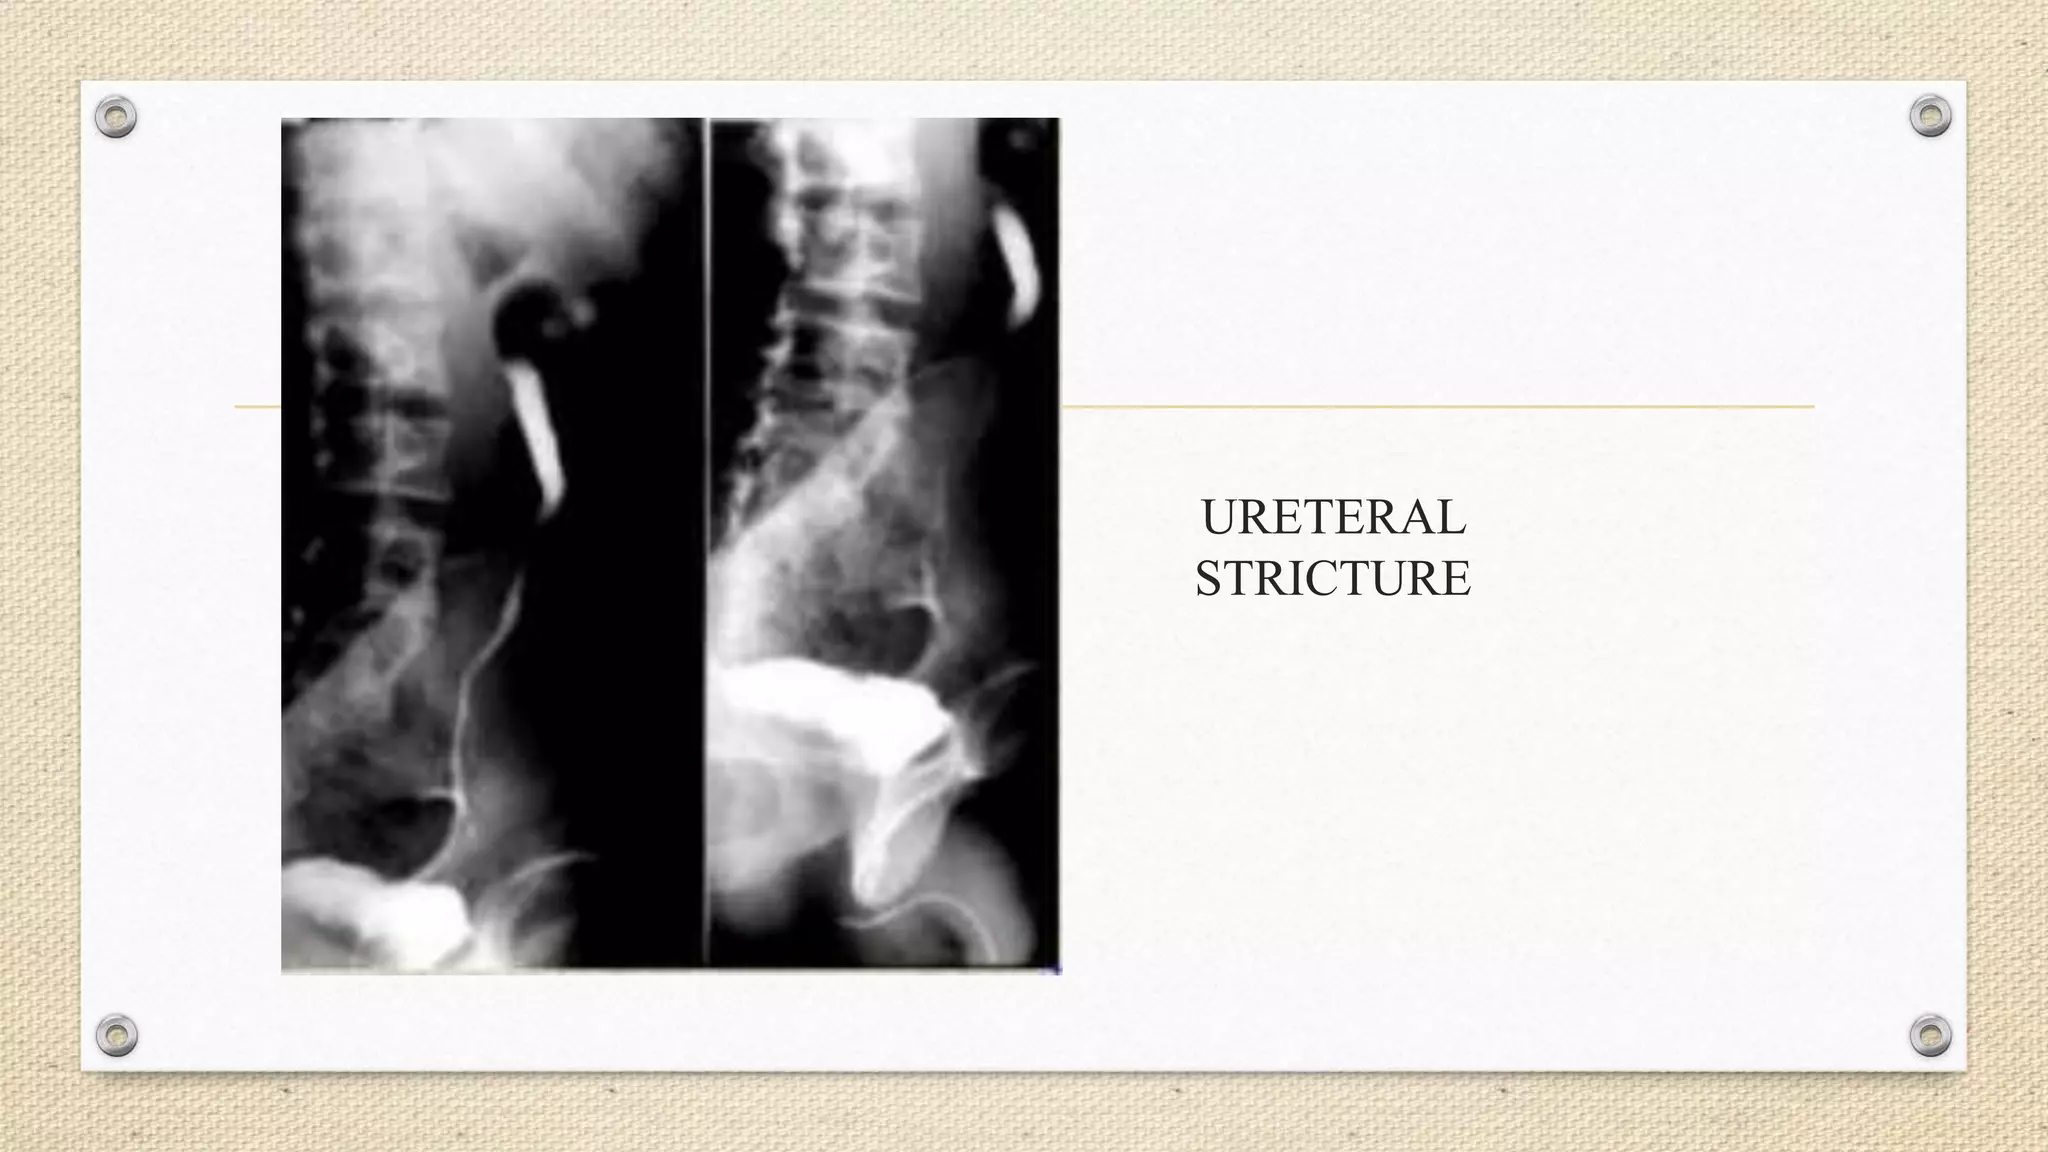

URETERAL

STRICTURE